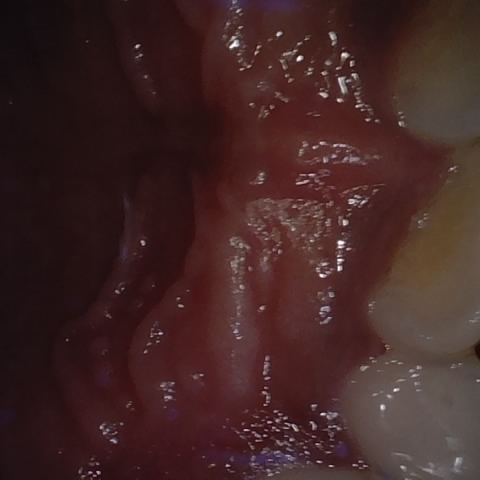

NHD39174

Annotated as "Good"